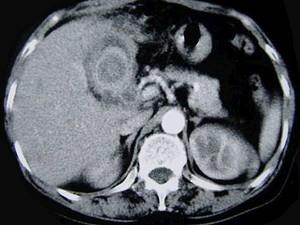

问题 女,55岁,右上腹痛多年,CT检查如图,最可能的诊断是 ( )

选项 A、胆囊癌 B、胆囊壁环状钙化 C、胆囊胆红素结石 D、胆囊混合性结石并胆囊炎 E、胆囊胆固醇结石

答案 D